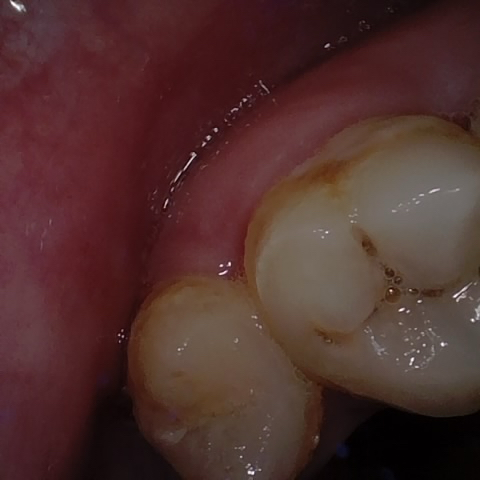

Annotated as "Good"